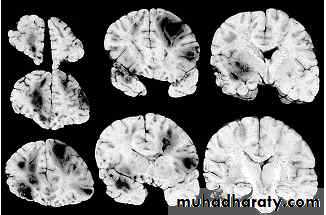

1. Diffuse Axonal Injury

Prolonged post-traumatic state in which there is loss of consciousness from the time of injury that continues beyond 6 hours.Occurs as a result of mechanical shearing at the grey-white matter interface.

This causes disruption and tearing of axons, myelin sheaths and blood capillaries.

Severity can range from mild damage with confusion to coma and even death.